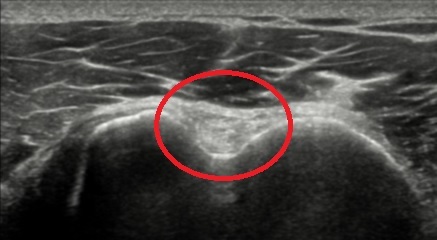

QUAL A ESTRUTURA ASSINALADA NA IMAGEM OBTIDA EM UMA ULTRASSONOGRAFIA DE OMBRO?

PORÇÃO EXTRA ARTICULAR DO TENDÃO DA CABEÇA LONGA DO BÍCEPS BRAQUIAL